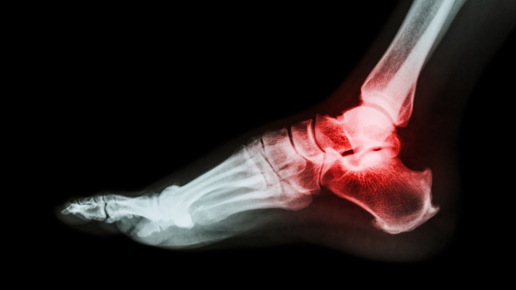

Человеческая стопа состоит из 26 костей, самая большая из них — это пяточная. Она служит естественным амортизатором и поэтому окружена жировой прослойкой, в которой локализуются сосуды и нервы. Пятка остро реагирует на любые внешние и внутренние негативные факторы болезненными ощущениями. Причин такого симптома множество. Иногда ощущения настолько сильные, что человек не может свободно передвигаться. Самой распространенной причиной, по которой болит пятка, больно наступать считается неудобная обувь...

Острая или ноющая боль в пятке невыносима в любом проявлении и сильно мешает жить полноценной жизнью. “Гвоздь”, который словно торчит в пятке, постоянно напоминает о себе при каждом шаге. Любой человек, который хоть раз в жизни испытывал это ощущение - знает, что от этого “гвоздя” очень хочется избавиться как можно скорее. Большинство людей считают, что если болит пятка, то это пяточная шпора. Однако, специалисты выяснили, что боль в пятке зачастую не связана с наличием шипа или «шпоры» на пяточной кости...